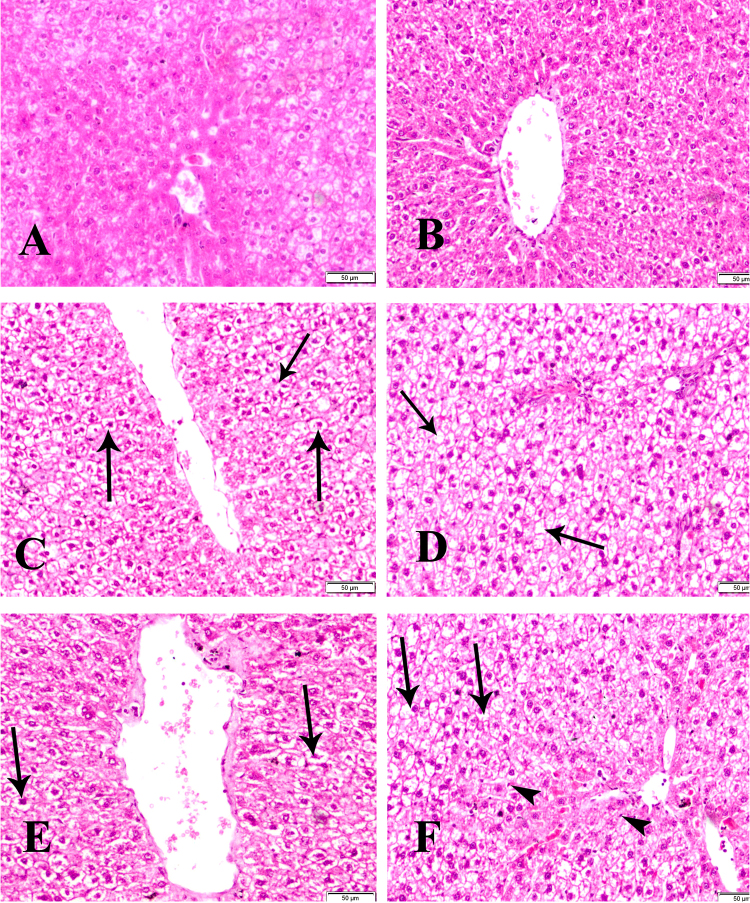

The liver revealed normal histological structure of control groups (groups 1 & 4) (Fig. 7A, B). Group 2 of dam showed hydropic degeneration and pyknosis of the nuclei (arrow) (Fig. 7C) and revealed sever hydropic degeneration and coagulative necrosis (arrow) in F1 female group (group 5) (Fig. 7D). In addition group 3 of dam showing increase in vacoulation of hepatic cells (arrows) (Fig. 7E) and revealed sever hydropic degeneration (arrows), coagulative necrosis, sinusoidal dilatation, pyknosis and proliferation of Kupffer cells (arrowheads) in F1 female group (group 6) (Fig. 7F).

Fig. 7.

Sections of liver of control group (group 1) (A) and F1 female (group 4) (B) showing normal histological structure. Group 2 of dam treated with low dose of BPA (C) showing hydropic degeneration and pyknosis of the nuclei (arrow) and of F1 female (group 5) (D) showing sever hydropic degeneration and coagulative necrosis (arrow). Group 3 of dam treated with high dose of BPA (E) showing increase in vacuolation of hepatic cells (arrows) and of F1 female (group 6) (F) showing sever hydropic degeneration (arrows), coagulative necrosis, sinusoidal dilatation, pyknosis and proliferation of kupffer cells (arrowheads) HE x 400.

Concerning the histopathological findings of the examined organs of our study which showed various lesions including degeneration in the epithelial lining of ovarian follicles, cystic dilatation of endometrial gland, submucosal leukocytic infiltration and increase in vaculation of hepatic cells with proliferation of kupffer cells, which were more sever in groups 3& 6 of both dam and their F1 female (Figs. 5–7) that could be explained by the results of DNA fragmentation previously mentioned. Sakuma et al. [46] supported our attribution where they mentioned that oxidative DNA damage has been implicated in a wide variety of pathological conditions. Additionally, our findings regarding the effect on the expression of ERβ, could attribute our histopathological lesions. In the same context Popa et al. [41] recorded that histopathologicial changes can be explained by estrogen activity of BPA. In this respect, our histopathologicial findings are in agreement with those findings detected by Newbold et al. [38] who mentioned that BPA has been reported to cause significant histological changes in the reproductive tract.